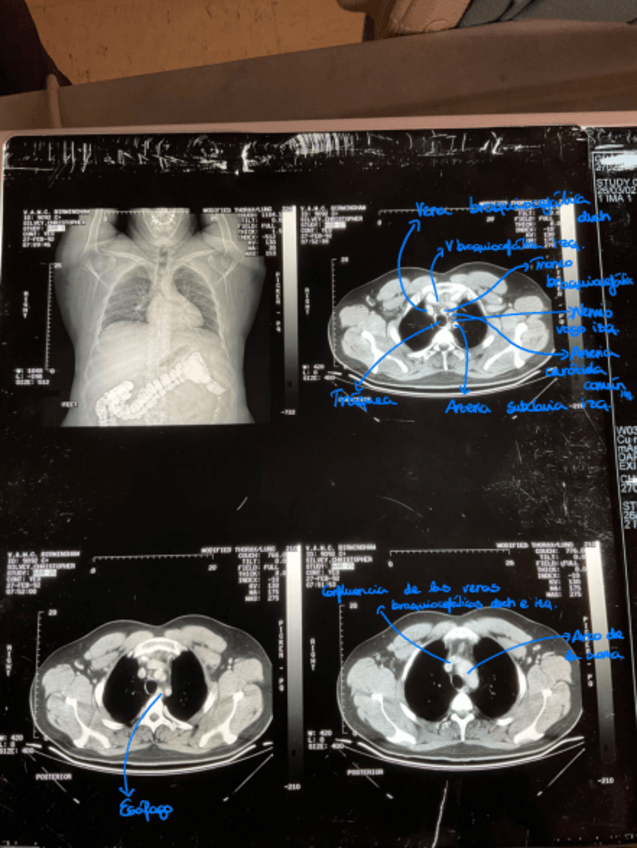

Imagenes-senaladas-ATI.pdf

Apuntes - Imagenes-senaladas-ATI.pdf